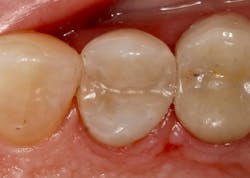

I have found that most posterior teeth can be restored using a single shade. In cases where the tooth structure is very discolored, coupled with a shallow tooth preparation, I opt for an opaque layer beneath my core shade. For anterior cases, the enamel shades offer enough translucency to give the restoration a lifelike appearance. I tend to opt for a core shade to restore chipped incisal edges, and the results have been terrific. Nothing’s worse than a patient coming back with an anterior composite restoration that didn’t hold up; it leads to patients losing confidence in your skills, sometimes negative reviews, wasted chair time, and lost profitability. Polishing this composite is very efficient and effective, and so far, it’s maintained its shine. From my assistants’ perspectives, simplifying my systems made it easier to learn, maintain inventory, and prepare for direct restorations. From my perspective, simplifying composite restorations allows me to reduce chair time, minimize waste, and predictably and efficiently place restorations that my patients love.

Results